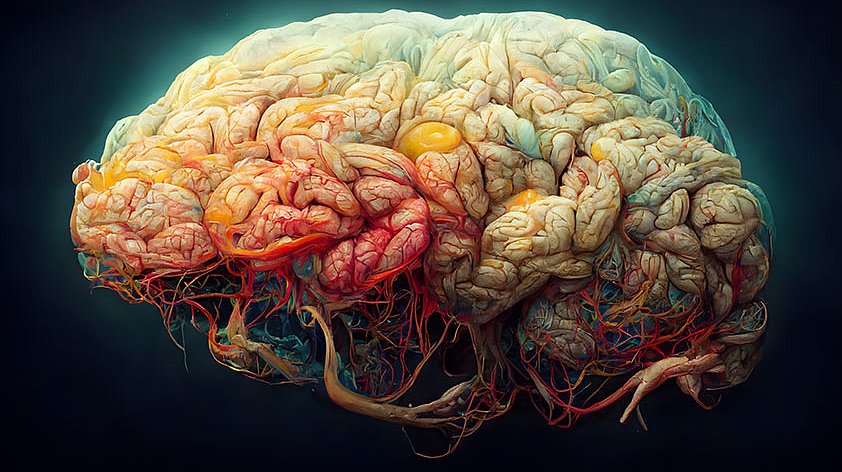

Коннектом мозга: визуализация связей и нейронных путей